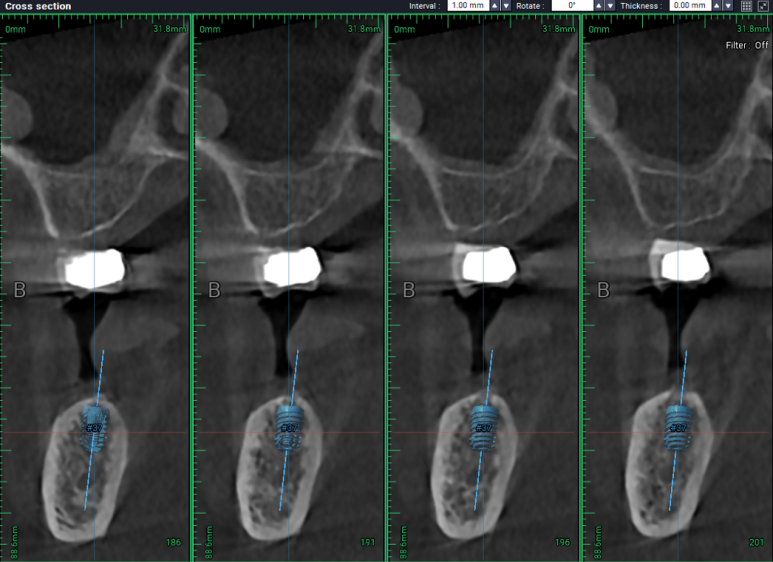

#34,36,37 자리에 임플란트를 식립할 예정이었어요.

비교적 뽑은지 오래되었던 #36,37 치아는 잇몸뼈가 넉넉하게 보였습니다.

두 큰어금니 부위는 하치조신경관(아래이틀신경)만 조심해서 적절한 임플란트를 심어놓으면 되었습니다.